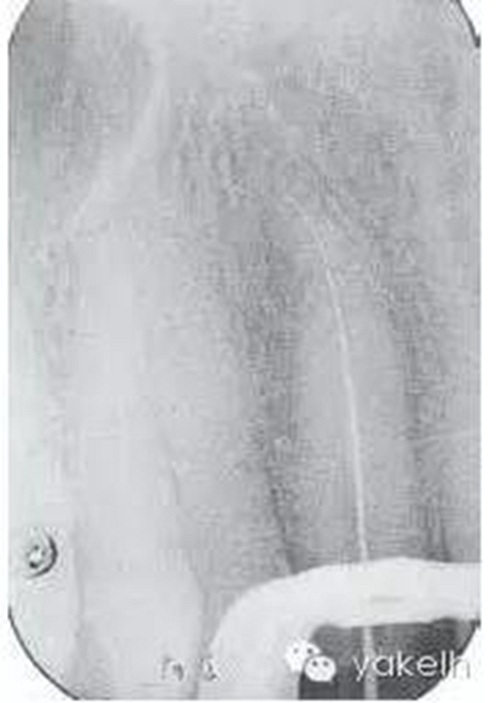

¤¤局麻下,制備上頜切牙印模;拆除12烤瓷全冠;評(píng)估患牙的可修復(fù)性;橡皮障隔離患牙,定位根管口,使用GG鉆和不銹鋼手用銼去除根管內(nèi)的牙膠;全程使用大量次氯酸鈉沖洗根管;根尖定位儀測(cè)量根管工作長(zhǎng)度,拍攝X線片確定(圖6.3.3);使用不銹鋼手用銼和鎳鈦旋轉(zhuǎn)器械進(jìn)行根管預(yù)備,EDTA沖洗根管,再用次氯酸鈉進(jìn)行終末沖洗;紙尖干燥根管;使用牙膠輔以根管封閉劑、采用熱垂直加壓技術(shù)充填根管的根尖5mm;建議樁核冠修復(fù)。

圖6.3.3 確定工作長(zhǎng)度的X線片顯示,12根管通暢至全長(zhǎng);特征是根管的根尖1/3向遠(yuǎn)中腭側(cè)彎曲。